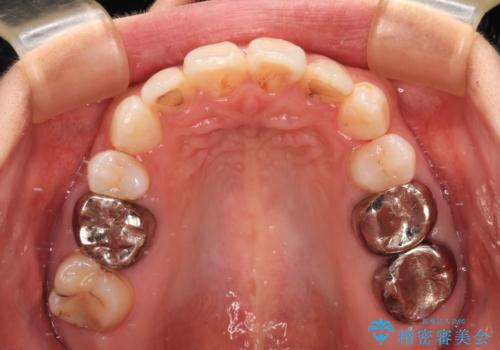

4本の歯を抜歯したことで、飛び出していた口元が引っ込み、横顔が大きく改善されました。

上下ともに歯列が前方に突出していたため、上下左右の第一小臼歯4本を抜去し、ワイヤー装置による矯正治療を行うこととしました。

左下奥歯にむし歯が認められるため、矯正治療後にセラミックインレーにて修復治療を行うこととしました。